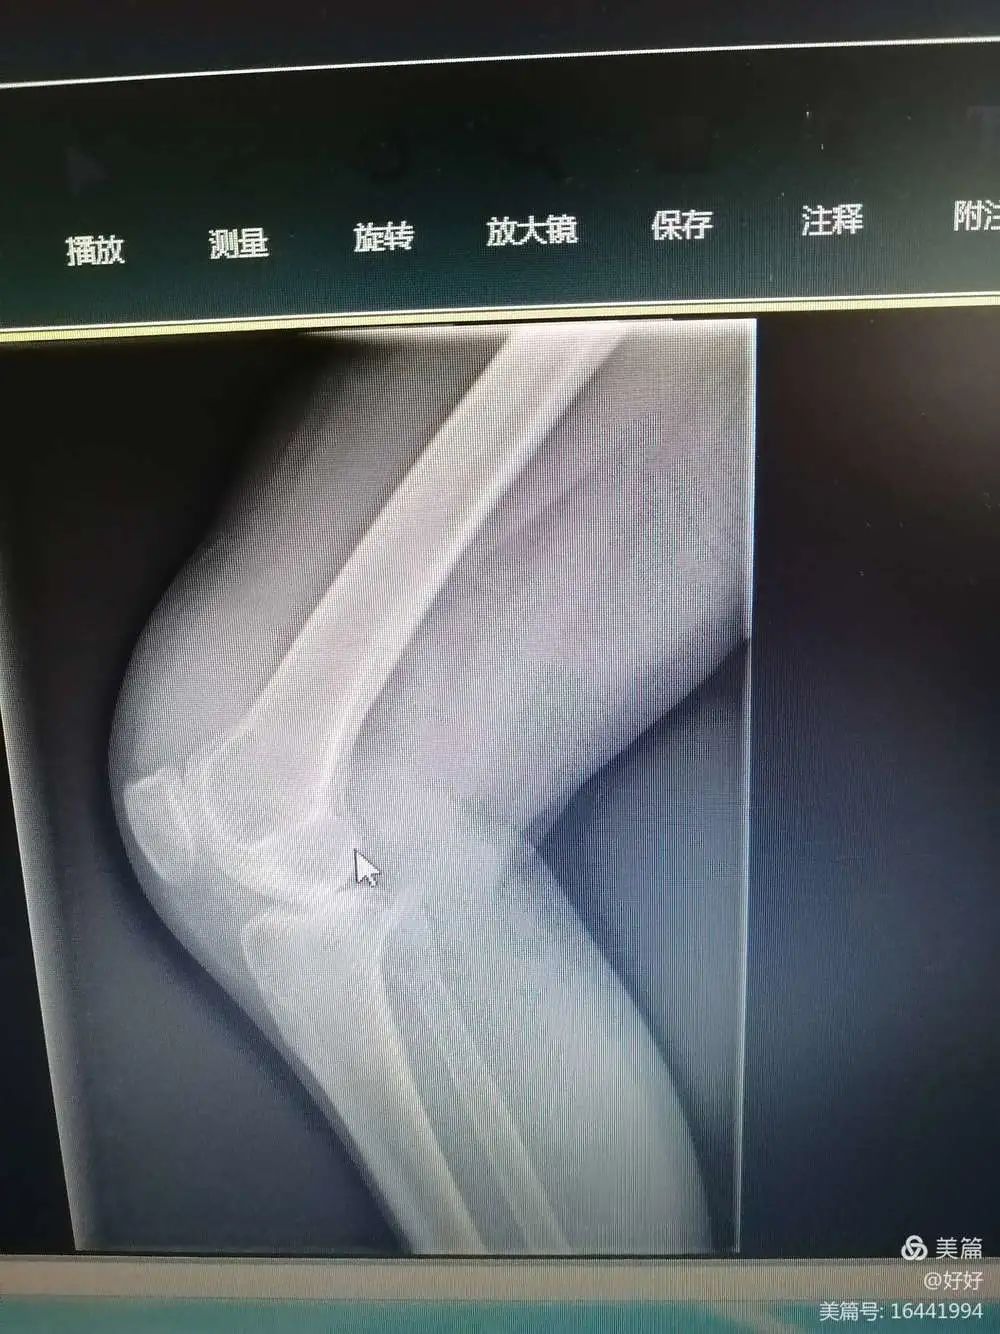

术前X线

李XX,男,55岁,外伤导致右膝关节疼痛30余年,患者30年前右小腿骨折,未行正确治疗,右膝关节活动完全受限,无法正常行走及日常生活,我科骨科团队予以行右膝人工关节置换,术后患者可以正常走路,且从事正常劳作。